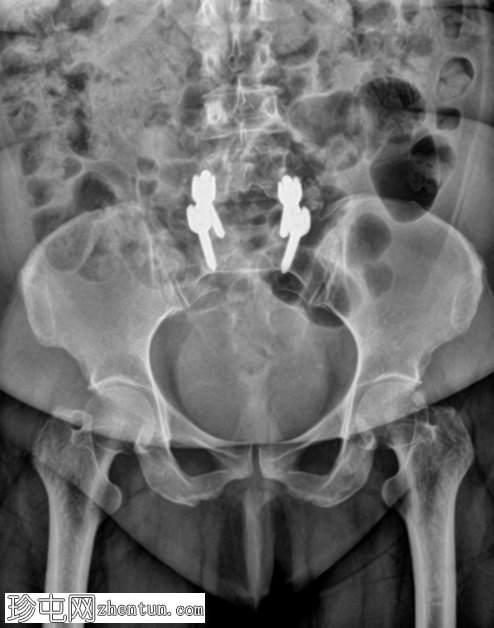

术后

X光片

6.png

正面

7.png

侧面

L5和S1节段间有脊柱内固定器械。

椎弓根螺钉和棒已置入。